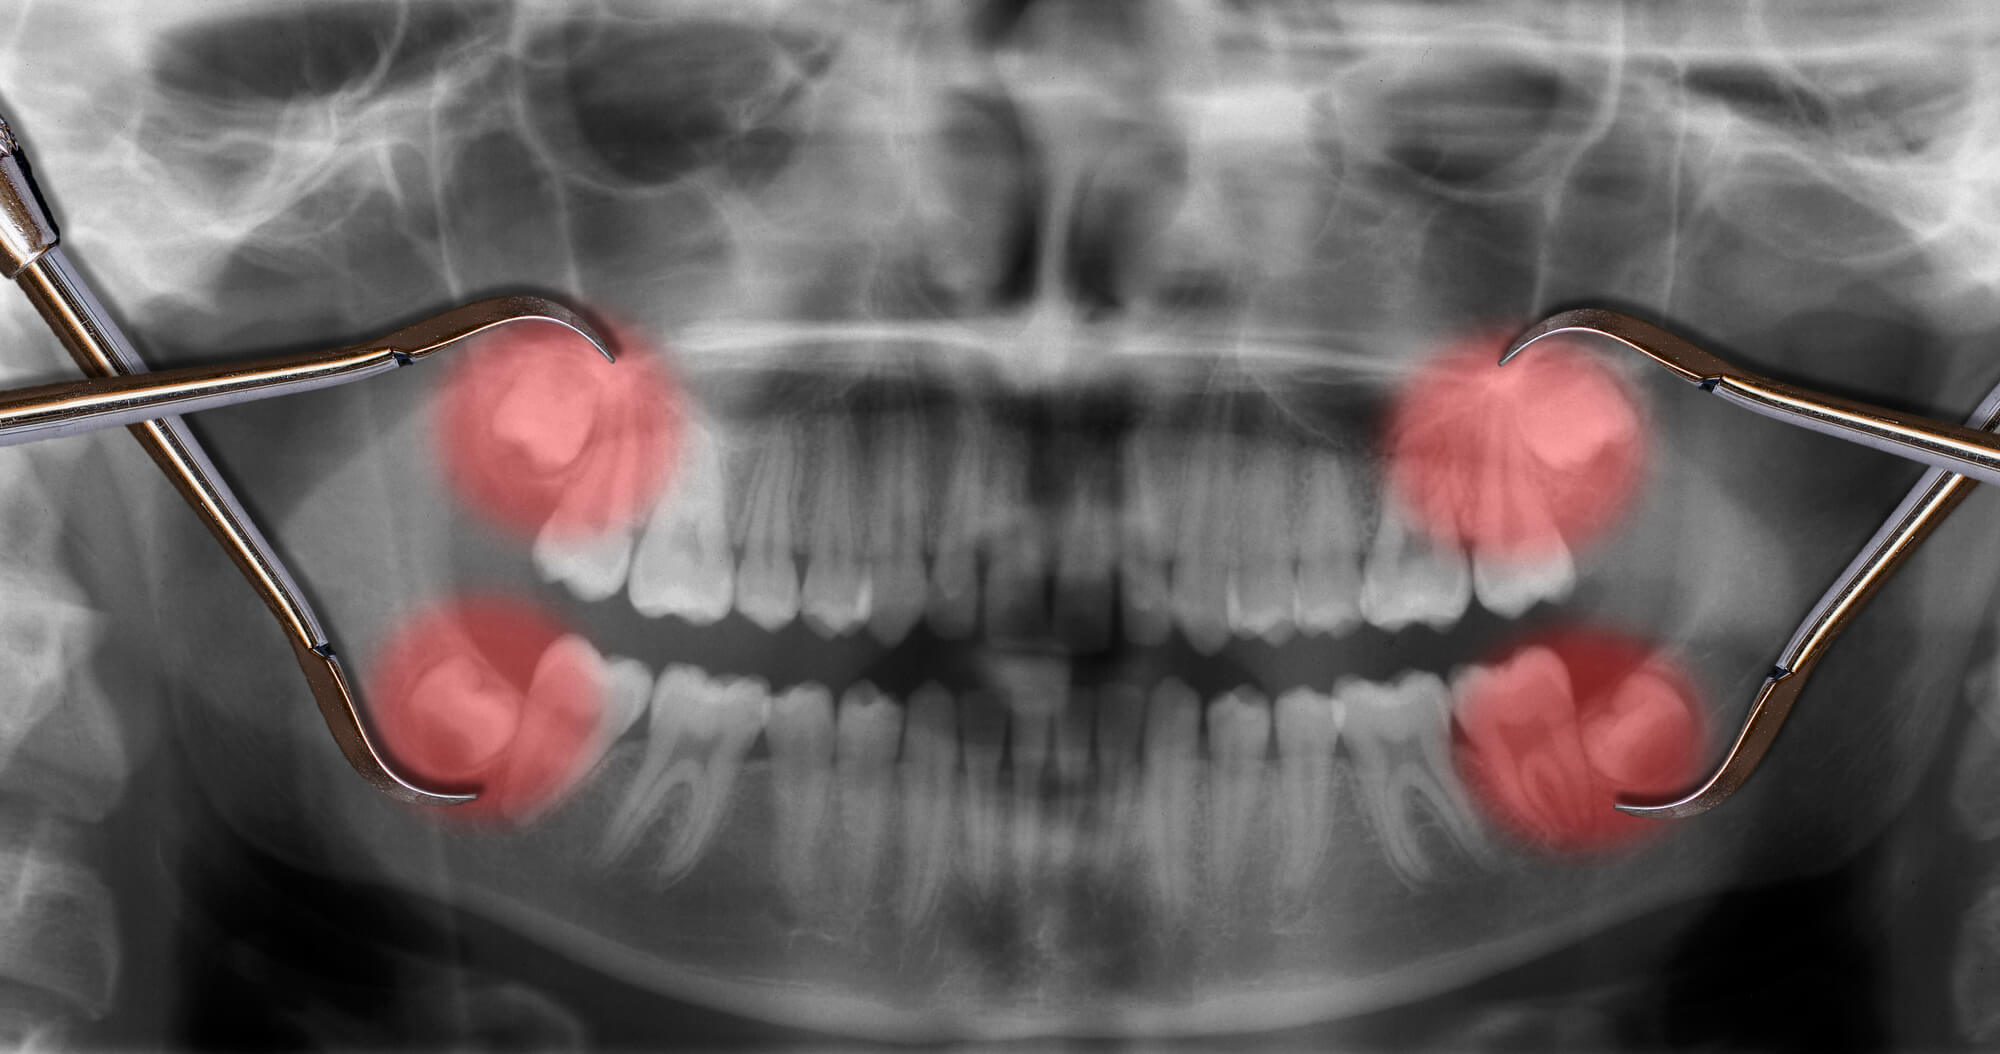

Wisdom teeth often lack the space to erupt properly in the mouth. This can lead to impaction, causing pain, infection, and damage to adjacent teeth. Dentists often recommend extracting impacted wisdom teeth to alleviate discomfort and prevent future issues.